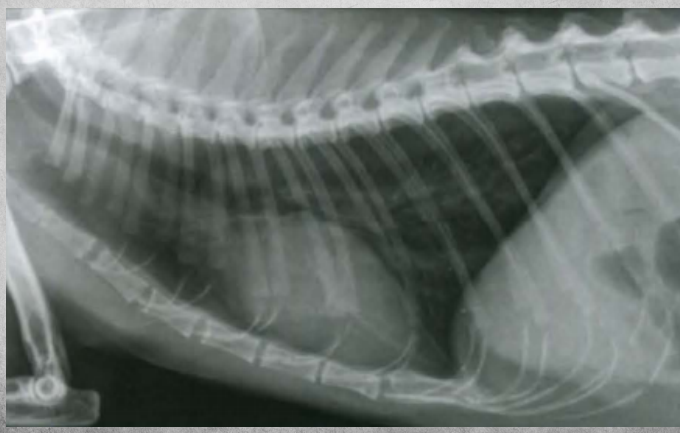

Q

What view is this?

A

right lat